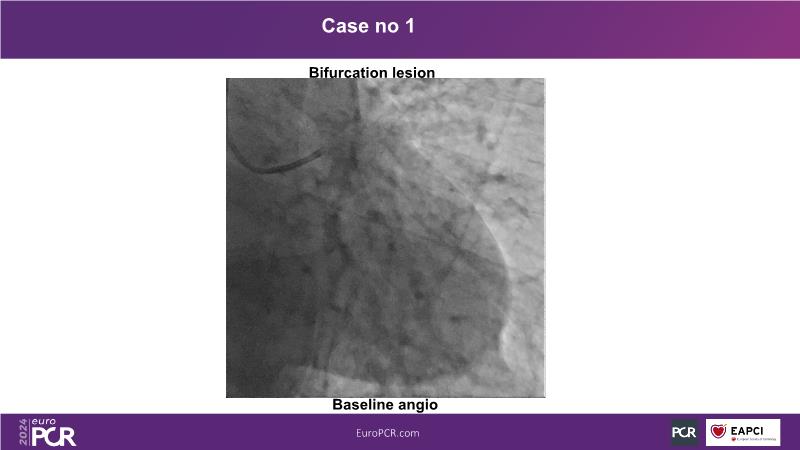

In this session, discover the effectiveness and safety of robotic PCI for both simple and complex lesions requiring additional devices like IVL, IVUS, laser, and FFR. Learn about the numerous benefits of robotics for patients and cathlab teams, including enhanced precision in wire navigation and stent positioning, full radioprotection, and reduced orthopedic injuries. Explore the growing interest in robotics within the interventional cardiology community, anticipate future technical advancements, and understand how AI will accelerate the integration of robotics and vice versa.

- To learn about a robotic PCI step-by-step from real-life experience